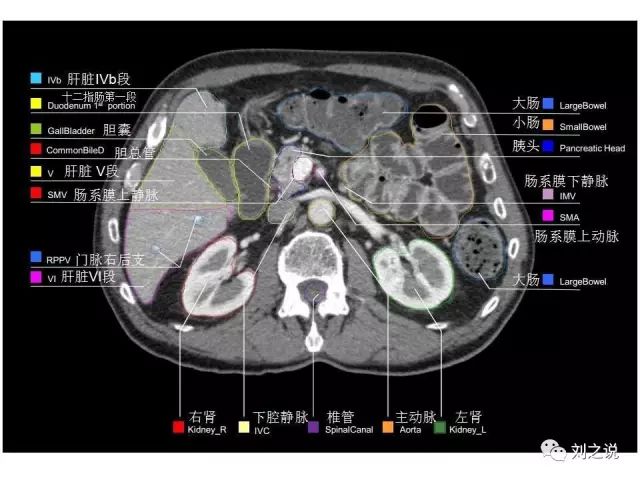

参考RTOG共识和3D-body解剖。

来源:刘之说